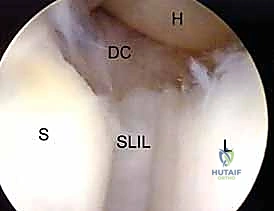

1. The Midcarpal Radial Portal (MCR)

- Location: Approximately 1 cm distal to the 3-4 portal. It is bounded radially by the ECRB tendon and ulnarly by the EDC tendons.

- Anatomy: This portal enters the midcarpal joint, providing a view of the scaphoid, lunate, capitate, and hamate articulations.

- Neurovascular Risks: Generally safe, but the superficial radial nerve branches can be in the vicinity more radially.

- Function: A primary viewing portal for midcarpal arthroscopy, allowing triangulation with the midcarpal ulnar portal for instrumentation. Essential for probing the SLIL and LTIL joint spaces for instability and assessing chondral lesions.

2. The Midcarpal Ulnar Portal (MCU)

- Location: Similarly located 1 to 2 cm distal to the 4-5 portal. It is bounded by the EDC and the EDM tendons.

- Anatomy: Enters the midcarpal joint, providing views of the lunotriquetral articulation, hamate, and capitate.

- Neurovascular Risks: The dorsal cutaneous branch of the ulnar nerve is at risk here.

- Function: Complements the midcarpal radial portal for triangulation, allowing instrumentation for débridement, loose body removal, or chondroplasty.